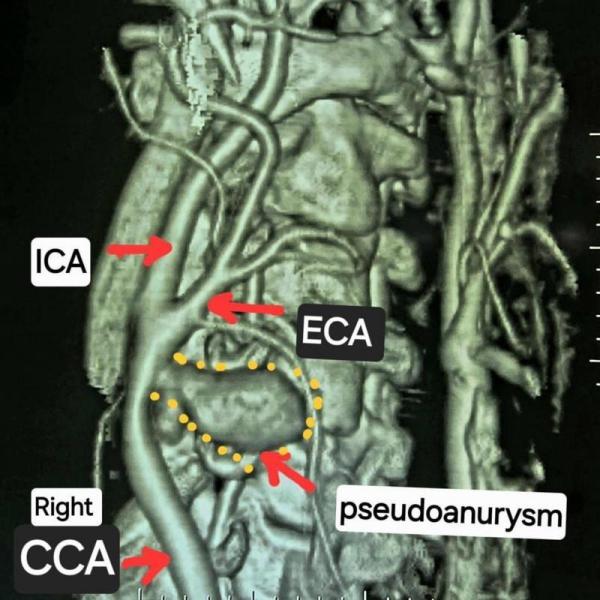

இந்த நிலை ஏன் ஆபத்தானது? Dr. Krishnakant Sahu இந்த ஸ்கேன் ராகுலின் நிலையை தெளிவுபடுத்துகிறது, அவரது வலது கரோடிட் தமனி, அதன் சிதைவு ஆகியவற்றைக் காட்டுகிறது.

Dr. Krishnakant Sahu இந்த ஸ்கேன் ராகுலின் நிலையை தெளிவுபடுத்துகிறது, அவரது வலது கரோடிட் தமனி, அதன் சிதைவு ஆகியவற்றைக் காட்டுகிறது.

மருத்துவப் பரிசோதனையில் ராகுலின் வலது பக்க கழுத்து நாளம் வெடித்திருப்பது தெரியவந்தது.

ராகுலின் கழுத்தில் வலது நாளம் வெடித்ததால், கழுத்துப் பகுதியில் ரத்தம் வேகமாக நிரம்பியது. தமனியைச் சுற்றி ரத்தம் தேங்கியதால் ஒரு பலூன் போன்ற அமைப்பு உருவானது.

இதனை மருத்துவ மொழியில் 'சூடோஅன்யூரிசம்' என்று அழைக்கிறார்கள்.